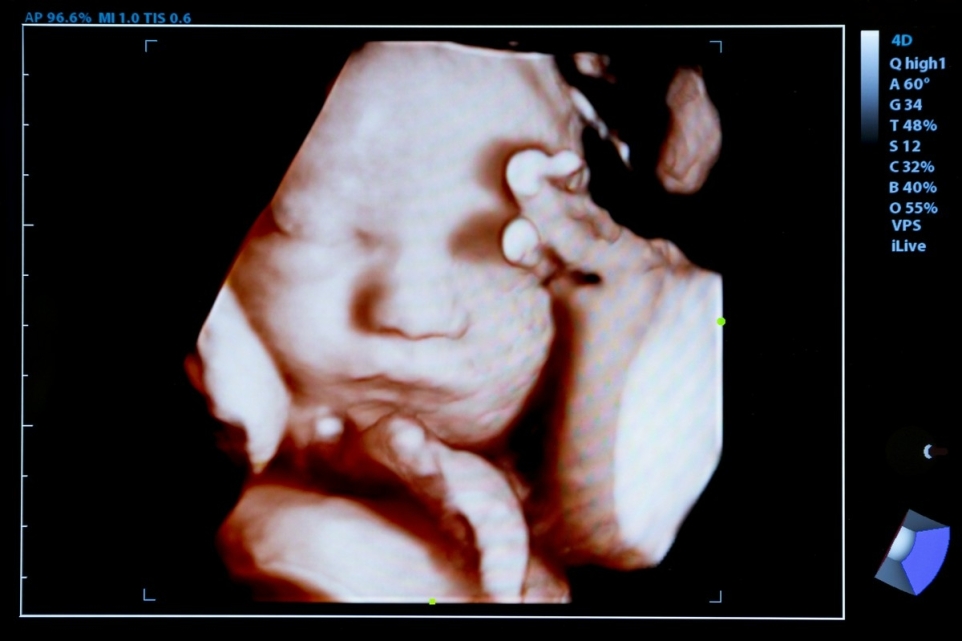

USG genetyczne to szczegółowe badanie ultrasonograficzne wykonywane w kolejnych etapach ciąży: w pierwszym (11.–14. tydzień), drugim (18.–24. tydzień) oraz trzecim trymestrze. Jego głównym zadaniem jest ocena biometrii płodu, analiza budowy poszczególnych narządów oraz pomiar przezierności karkowej (NT). Uzyskane parametry pozwalają oszacować prawdopodobieństwo wystąpienia nieprawidłowości genetycznych, takich jak zespół Downa (T21), zespół Edwardsa (T18) czy zespół Pataua (T13).